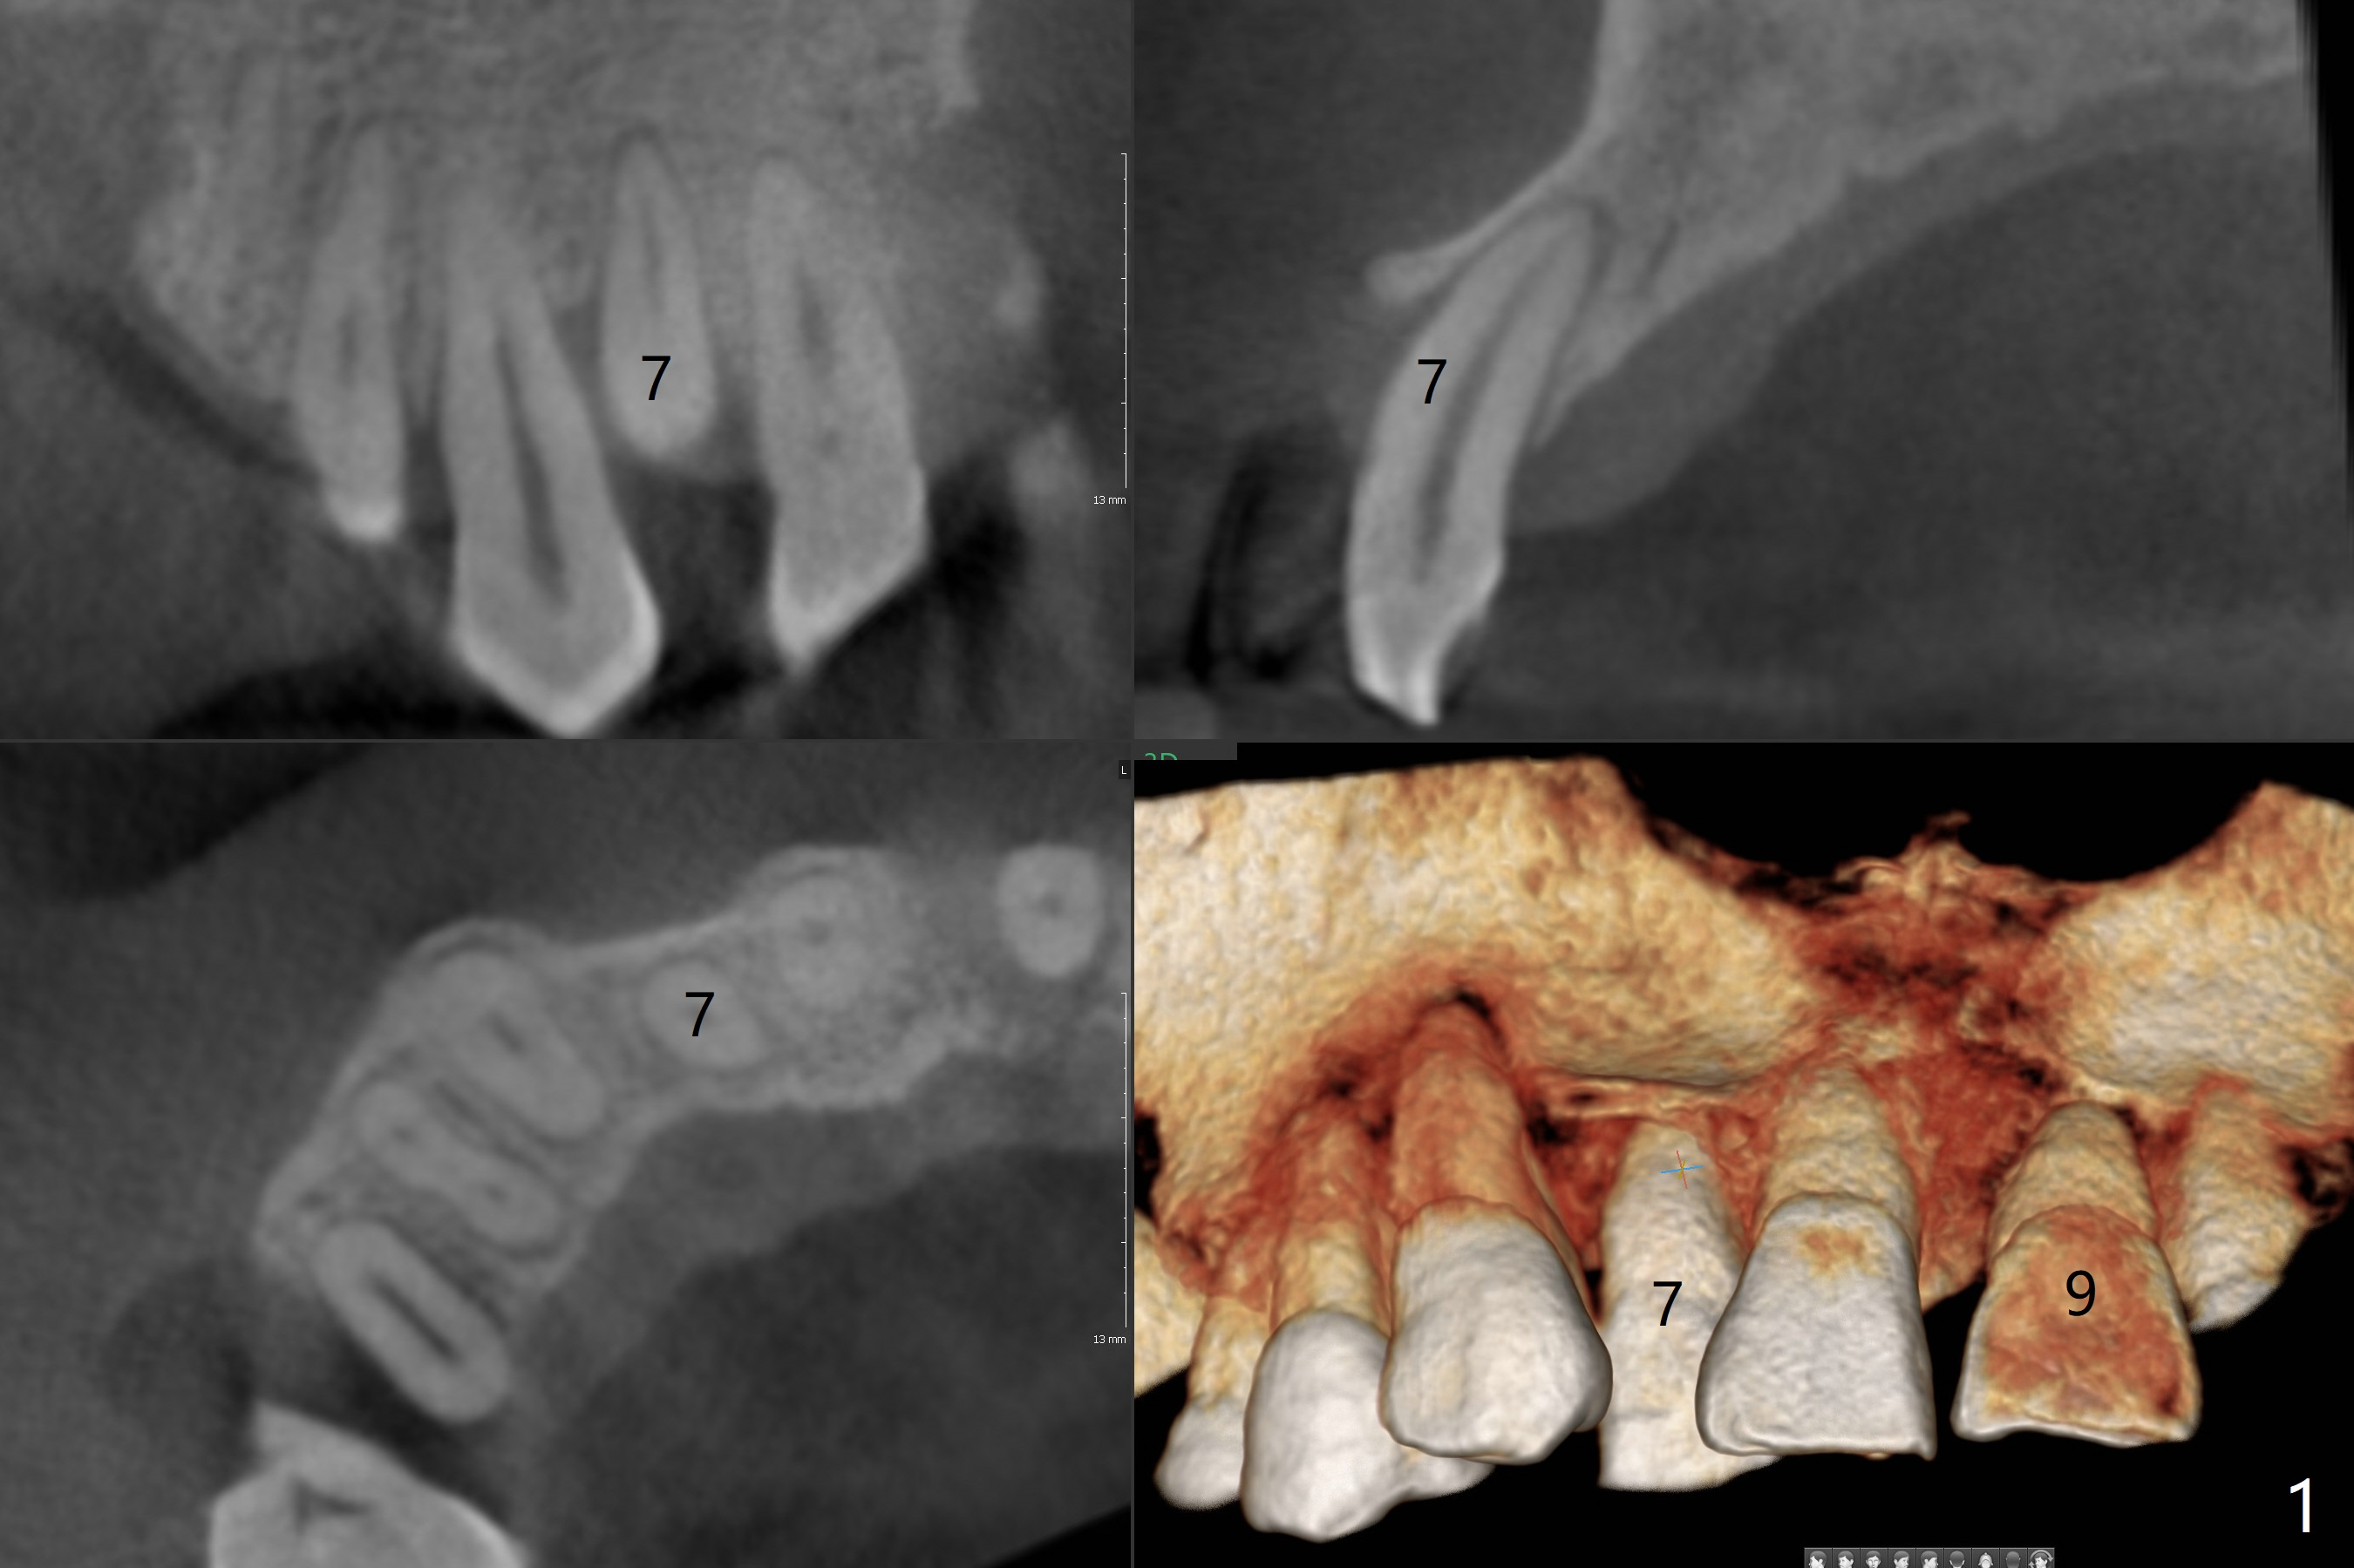

A 47-year-old man has history of chronic periodontitis and bruxism.  After implants at 19, 3, and 9 with improvement in oral hygiene, he has unabated wish to correct #7 cross bite (Fig.1).   The upper dental midline deviates to the right.  When the implant at #9 osteointegrates, align the mesial surface of the immediate provisional to the facial midline.

Take pre-orthodontic photos and impression for model surgery.  Warn repeatedly the patient of complications, including aggravation of chronic periodontitis and loss of several teeth.  Comprehensive orthodontics seems to be necessary (upper and lower arches).  The tooth #23 may be extracted with immediate implant.